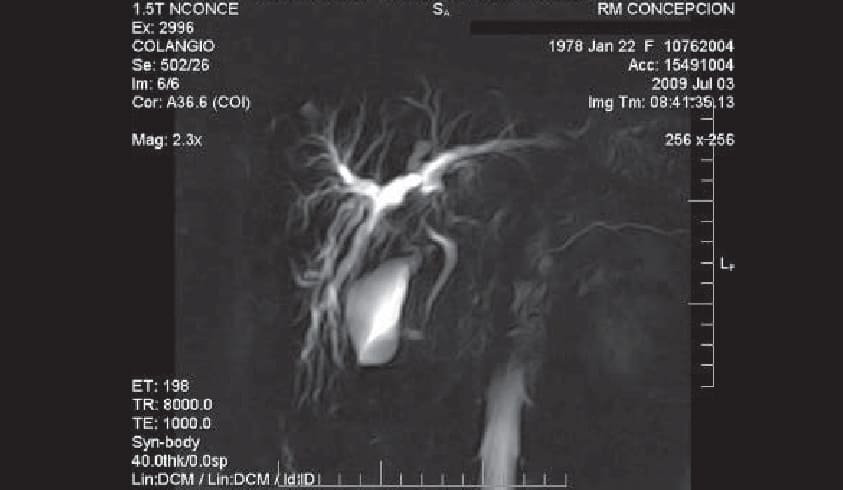

COLANGIOGRAFÍA

La CPRE es un procedimiento que permite examinar los conductos pancreáticos y de la bilis. Un endoscopio especial se introduce a través de la boca y hasta la parte superior del intestino delgado.